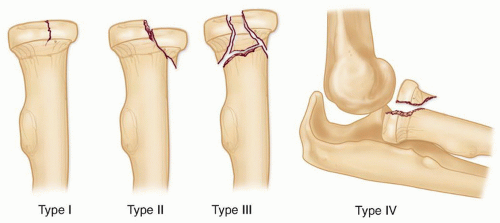

What classification is used to classify radial head fractures?

Mason classification; based on degreee of dispalement & intra-articular involvement